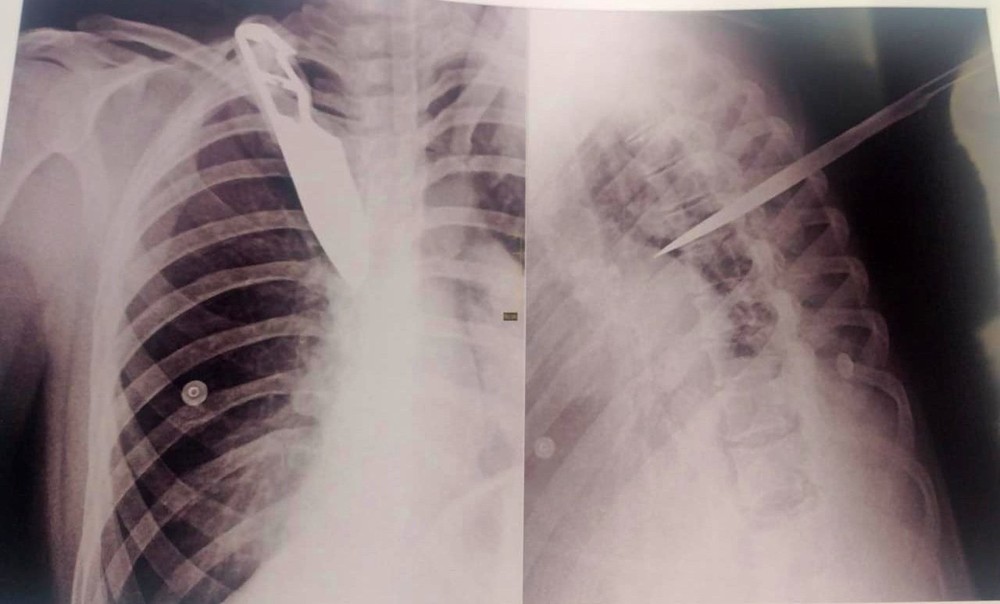

Uma imagem de um exame de raio-X mostra a faca cravada nas costas da mulher atingida pelo ex-companheiro, que é detento e estava em ‘saidinha’ de fim de ano, durante uma discussão, na terça-feira (28), em Garça (SP).